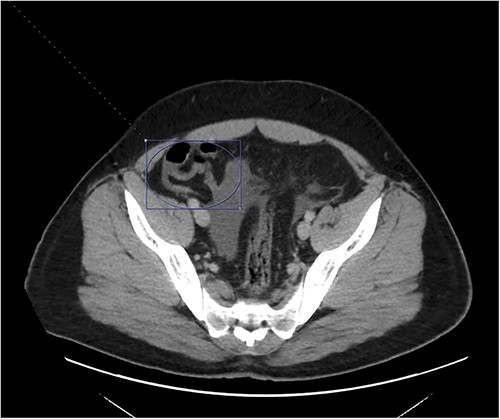

On presentation to the emergency department (ED), he was afebrile and normotensive with blood pressure in the 120s/80s though he had sinus tachycardia (heart rate 120–130 s). His abdomen was soft and diffusely tender with point tenderness at McBurney’s point and negative Rovsing’s sign. He had no signs of frank peritonitis. His complete blood count revealed leukocytosis (WBC 11K/μl), lactic acidosis (lactate 3 mmol/l), and mild transaminitis with AST 72 and ALT 101. An intravenous (IV) contrast-enhanced computed tomography scan of the abdomen/pelvis demonstrated a mildly dilated appendix (~8 mm) with surrounding fat stranding but no appendicolith, perforation, or abscess (Fig. 1). Interestingly, a partial portal vein (PV) and superior mesenteric vein (SMV) thrombosis were also noted (Fig. 2). Initial blood cultures were collected, which remained without growth.

A hyperemic and inflamed appendix can be seen without an abscess, perforation, or appendicolith.